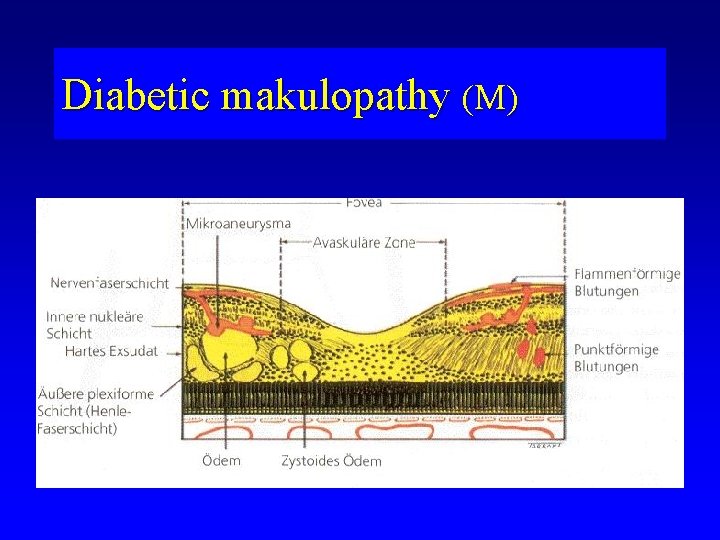

Diabetic maculopathy (M) • affects 33% of diabetic patients after 8 -10 years of duration of disease • the most common cause of vision loss in diabetic retinopathy

Diabetic makulopathy (M)

Diabetic makulopathy (M) • Macular area is a predilection site for edema formation Microangiopathy leads to ischemia, fluid accumulation, formation of microcysts and cysts Hard exudates (lipid accumulation) occur on the boundary of ischemic and normal retina

Diabetic makulopathy (M)